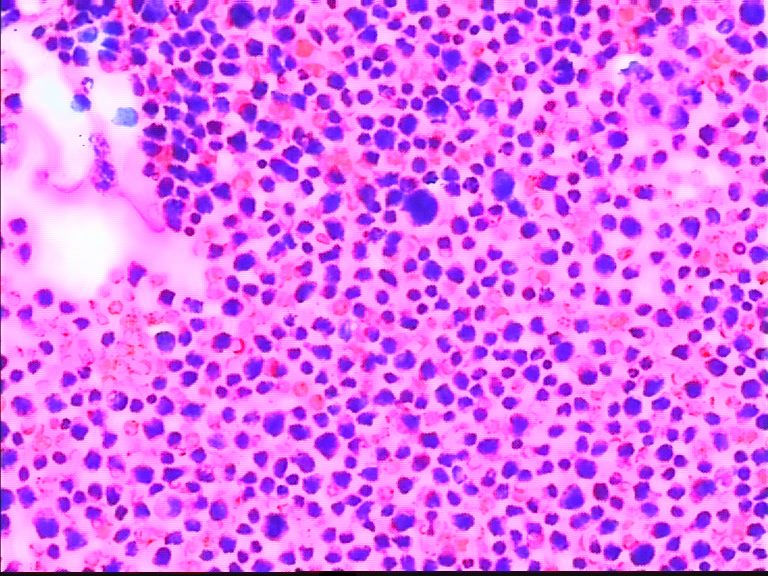

68岁,男,CT示胆囊有增粗影,余检查无殊,临床考虑胃肠道肿瘤。肿瘤指标均正常。

片子里面这种细胞很多,让我总是觉得有问题,但是又不敢报癌,拍的还是最典型的 感觉核好像看起来有点奇怪,也不知道是什么原因

这些图片应该是干性固定的吧,细胞退变明显;我刚看这些涂片的时候;如果不是楼主提示是胸水;我以为还是在看骨髓的HE涂片;请注意不要只注意哪些大细胞,还要仔细看那些背景中有核的细胞,大小不等;有异型性;请楼主提供病人的外周血象结果和其他相关临床情况;如果那些大细胞是巨核细胞,那这个病人很可能是白血病或淋巴造血肿瘤;另要注意鉴别其他未分化癌或肉瘤。

同样考虑恶性肿瘤,首选 淋巴造血系统疾病。期待继续!

个人倾向低分化腺癌。如果是淋巴造血系统的肿瘤,胞浆太多了些。

背景中的细胞也是有些大小不一,考虑淋巴造血系统的肿瘤,期待进一步的结果

免疫组化结果 最后为淋巴瘤